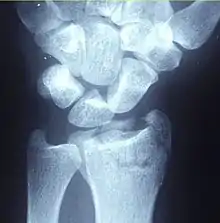

A Colles fracture as seen on X-ray: It is a type of distal radius fracture.

A distal radius fracture, also known as wrist fracture, is a break of the part of the radius bone which is close to the wrist.[1] Symptoms include pain, bruising, and rapid-onset swelling.[1] The ulna bone may also be broken.[1]

In younger people, these fractures typically occur during sports or a motor vehicle collision.[2] In older people, the most common cause is falling on an outstretched hand.[2] Specific types include Colles, Smith, Barton, and Chauffeur's fractures.[2] The diagnosis is generally suspected based on symptoms and confirmed with X-rays.[1]